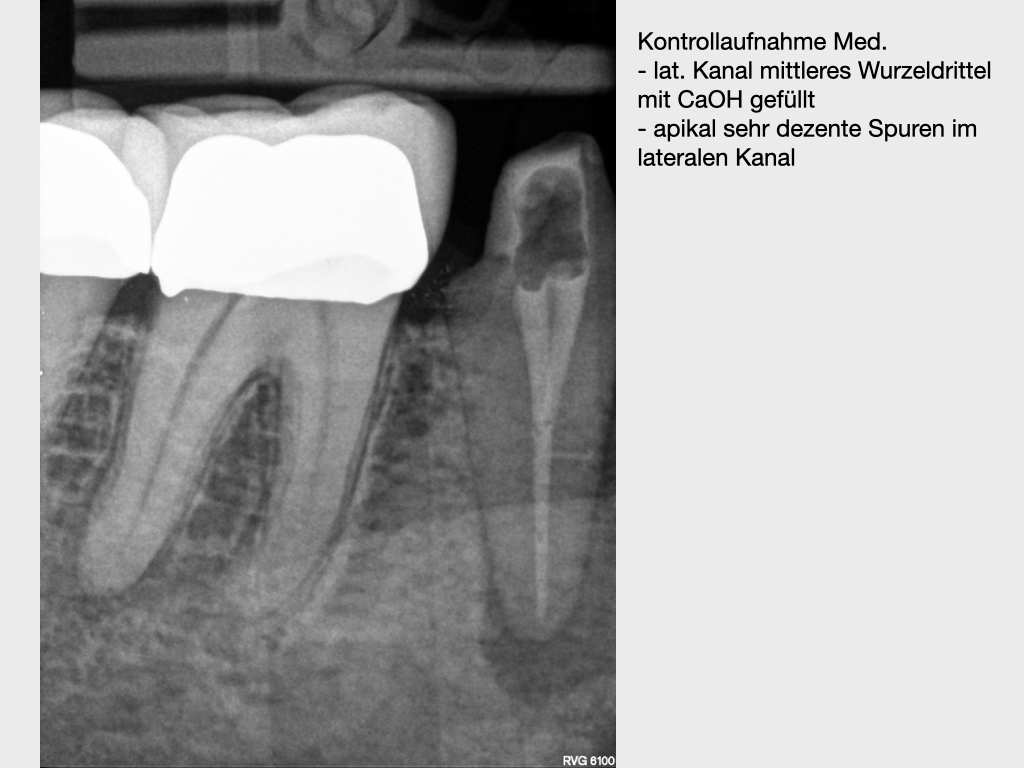

lateraler Kanal.014

Lateraler Kanal